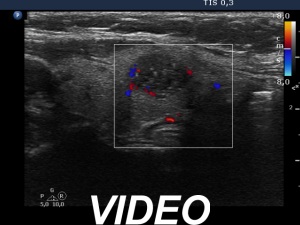

Ultrasonography. The thyroid was echonormal. There was hypoechoic nodule in the left lobe. The nodule had numerous echogenic granules and lines. Video record proved that these are clearly related to ventral cystic areas, therefore these are back wall cystic figures caused by posterior enhancement. The nodule showed taller-than-wide sign.

Comment. This case illustrates why is video clearly superior to still images in analyzing thyroid nodules. Viewing the still image on transverse section (first image in the list), the intranodular echogenic figures seem to be microcalcification. However, video clearly proved the presence of tiny cystic areas ventral to these echogenic figures.